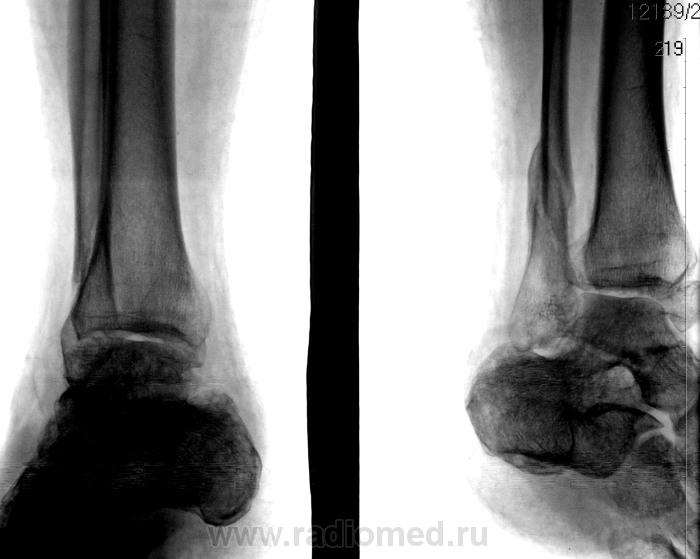

Сняли ГИПС. 2.

Не срослось почему-то.

Да не срослось...

Да и ложный сустав в районе внутренней лодыжки образовался.